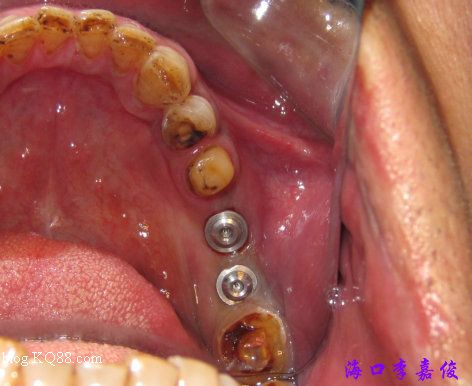

術(shù)后

術(shù)后全景